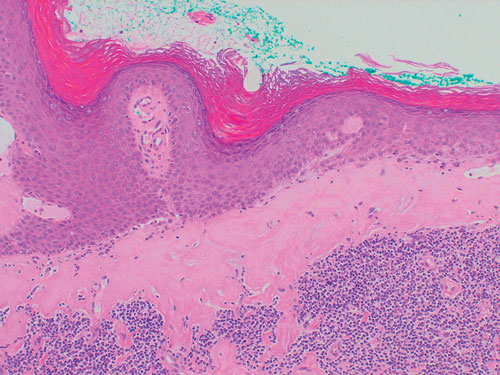

5: Dermatitis of the vulva

Dermatitis, showing poorly defined erythema extending beyond the flexures with excoriations.